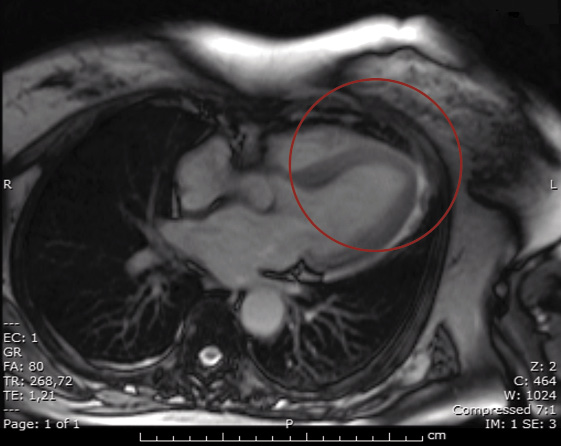

L’ecocardiogramma eseguito in urgenza evidenziava un quadro di ipo-acinesia dell’apice con aspetto globoso (aspetto Tako-Tsubo-like) associato a moderata depressione della funzione sistolica globale. In seguito si eseguiva una risonanza magnetica cardiaca (Figura 2) che permetteva di escludere una miocardite; la coronarografia eseguita a completamento diagnostico escludeva stenosi coronariche emodinamicamente significative confermando quindi l’ipotesi di sindrome Tako-Tsubo.

Figura 2. RMN cardiaca – dilatazione apicale del ventricolo sinistro

Nel caso da noi descritto la disfunzione ventricolare era correlata a un interessamento della porzione apicale del ventricolo sinistro come documentato sia all’ecocardiogramma sia allo studio emodinamico. Inoltre, mediante RMN cardiaca venivano escluse alterazioni del miocardio sia di tipo ischemico sia miocarditico, mentre si confermavano le alterazioni settoriali della cinetica ventricolare permettendo di porre diagnosi di sindrome di Tako-Tsubo. La sindrome di Tako-Tsubo, nota anche come Apical Ballooning Syndrome, è un’entità di recente definizione caratterizzata da disfunzione ventricolare con caratteristiche cliniche simili alla sindrome coronarica acuta; essa è spesso precipitata da eventi “stressanti” sia di natura psichica, sia soprattutto fisica e tipicamente è transitoria e con buona prognosi [8-10].